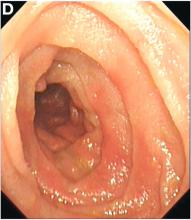

Double-balloon endoscopy revealed patchy redness and congestion at two sites between 50 cm (Figure C) and 150 cm (Figure D) from the pylorus. Some time after the patient was admitted, his symptoms deteriorated so much so that he attempted suicide.